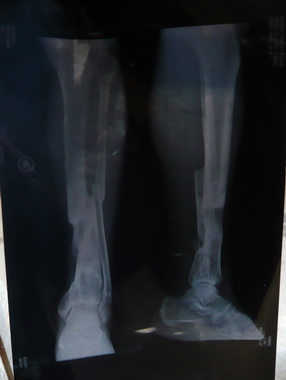

宋基福,男,江西省万载县三兴镇红旗村人,2004年在福建打工,后来以开出租摩托养家糊口。 2004年8月18日当天,和平常一样骑摩托车出门,不幸的是,当天发生了车祸,被另一辆摩托前轮撞到他的小腿, 导致右脚胫骨和腓骨多处骨折(从第一张X光片可以看出),另外,骨折处的肌肉和皮肤破坏得很严重, 整个右脚骨折处就大概剩下1/4正常皮肤,肌肉腐烂严重,属于严重的开放性骨折,其状况惨不忍睹!

由于他的家庭无力承担昂贵的医疗费用,在福建当地医院治疗一个星期后,考虑回家治疗。 因此,家人把他接回了本地,回到了江西省万载县三兴镇红旗村。开始,请本地的诊所医生到家为他打点滴消炎,防止皮肤和 肌肉溃烂,同时,我方也为他特意配置了外敷的中草药,促进肌肉和皮肤的生长,经过一段时间的治疗后,皮肤和肌肉基本复合, 但此时骨折处的骨头还没有丝毫的生长迹象。我方根据他皮肤和肌肉基本复合的情况下,对骨折处进行贴膏药治疗,随着疗程的深入, 脚不再肿了,开始慢慢的有骨痂的出现,他本人和家人看到这种情况是万分高兴。然后继续用我方的膏药治疗,最后终于康复。

第二张X光片是康复后自己去县人民医院拍的,当时医生看了都难以相信,但事实就是如此。 由于是农民,为了生计是必须下地干活。他本人康复后害怕不能挑重担,后来经过他的尝试,可以挑到100多斤的担,基本不会 影响到他干农活。把一个家庭从不幸的边缘拉了回来,现在,他们一家的生活越过越好!